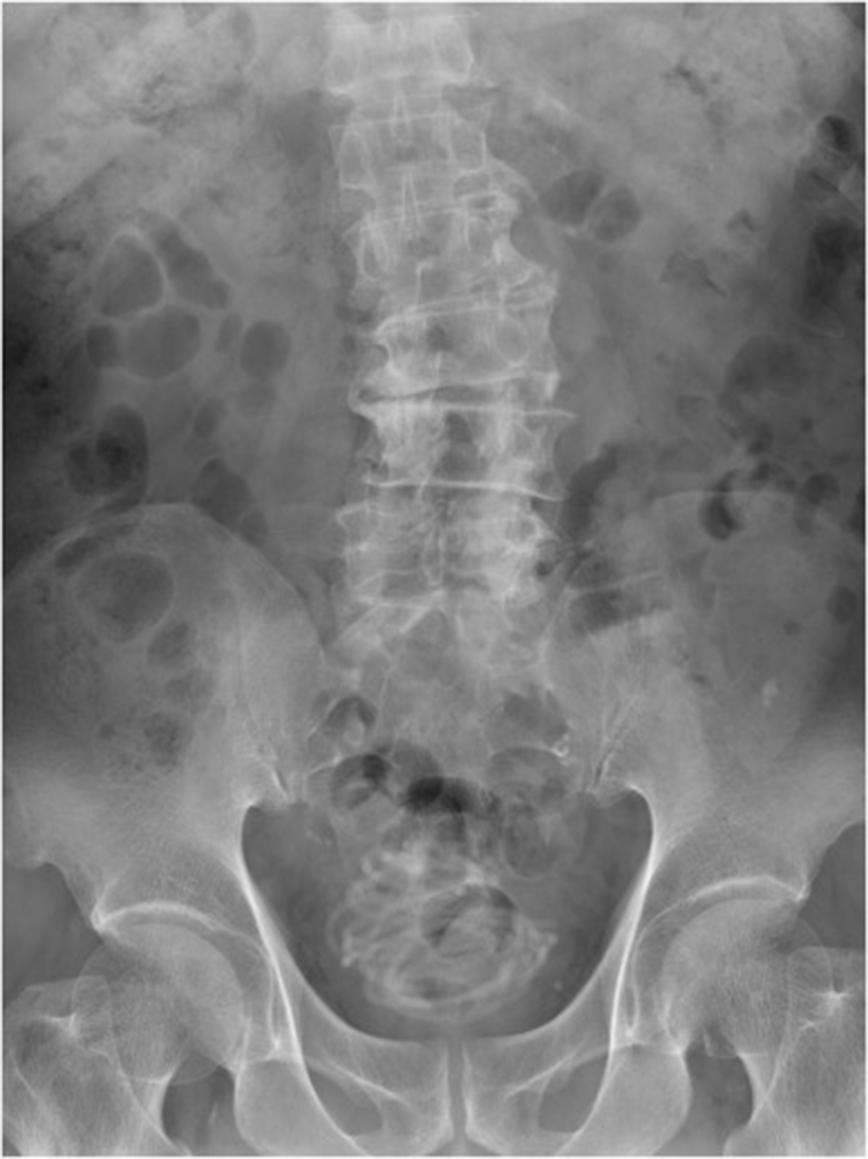

Τότε, υποβλήθηκε σε εξετάσεις και οι γιατροί δεν πίστευαν αυτό που έβλεπαν, αφού βρήκαν «ένα μεγάλο αντικείμενο συνοδευόμενο από σκιές». Έτσι, του έκαναν ακτινογραφία που αποκάλυψε πως ήταν «ένα συρμάτινο τυλιγμένο ξένο σώμα», με τον 79χρονο στη συνέχεια να παραδέχεται πως έχωσε το σχοινί στο πέος του, με αποτέλεσμα να κολλήσει μέσα, αν και δεν αποκάλυψε ποτέ τον λόγο που προέβη σε αυτή την πράξη.